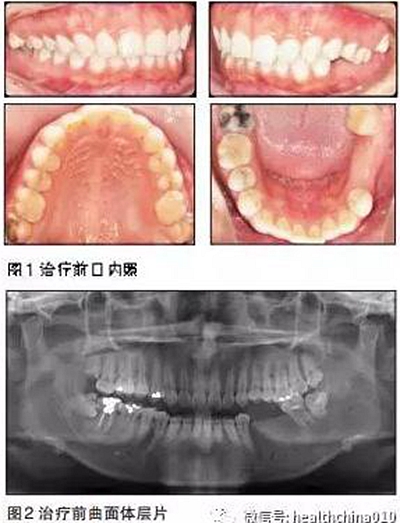

患者基本情況

患者女性,29歲。主訴:15年前左下后牙爛牙,在當(dāng)?shù)匮揽崎T診拔除,未給予修復(fù)。

近15年來患者由于左側(cè)牙齒無法咬碎食物,一直用右側(cè)后牙咀嚼,自覺臉型逐漸不對稱,要求修復(fù)左下后牙恢復(fù)咀嚼功能。體健,無吸煙史。

臨床檢查

患者臉型不對稱,右側(cè)大于左側(cè)。

牙周情況尚可,有少量牙結(jié)石,牙齦無明顯紅腫。35、36缺失,25、26過長,17與47,27與37正鎖牙合,咬合時26、27的牙尖頂?shù)綄︻M缺牙區(qū)牙槽嵴黏膜上。37、47死髓牙。

全口曲面體層片顯示:35、36缺失,缺牙區(qū)牙槽骨有足夠的骨高度,47未行根管治療,38、48近中阻生,18殘根,28頰面深齲近髓。